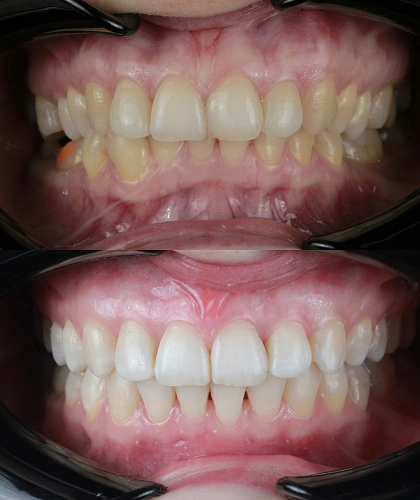

Клинический случай:

Рассмотрим пример ортодонтической коррекции на брекет-системе Damon Q. В данном случае срок лечения составил 1 год и 10 месяцев. За этот период удалось решить несколько важных задач:

• Устранение скученности зубов

• Коррекция наклона верхнего зубного ряда

• Удаление сильно разрушенного зуба на нижней челюсти и закрытие образовавшегося промежутка своими зубами

• Откорректированный прикус и центры зубных рядов

Работа была выполнена врачом-ортодонтом Глуховой Т.А., который тщательно подошел к каждому этапу лечения, чтобы достичь оптимального результата.